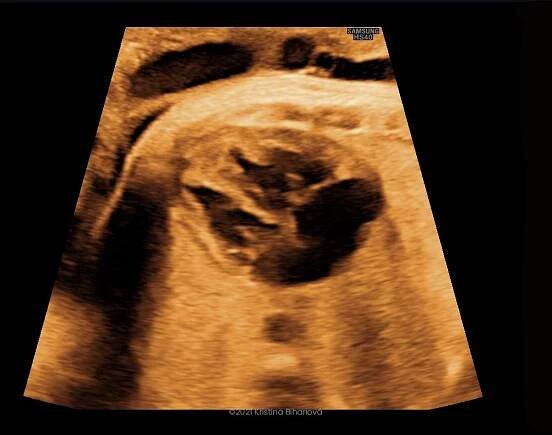

3D sonografia / 3D ultrazvuk - Druhý trimester - Srdce

Jaký je rozdíl mezi 3D a 4D ultrazvukem?Snímek 3D je dokonale plastická fotografie vašeho miminka, zcela reálná v daném čase a prostoru. V případě 4D zobrazení jde technický pokrok ještě dále a vy máte díky této technologii možnost vidět i reálný pohyb miminka natočený na videozáznam.

3D ultrazvuk je lékařská ultrazvuková technologie, často používaný v porodnické ultrasonografii (během těhotenství), poskytující troj-dimenzionální obrázek plodu. Wikipedie